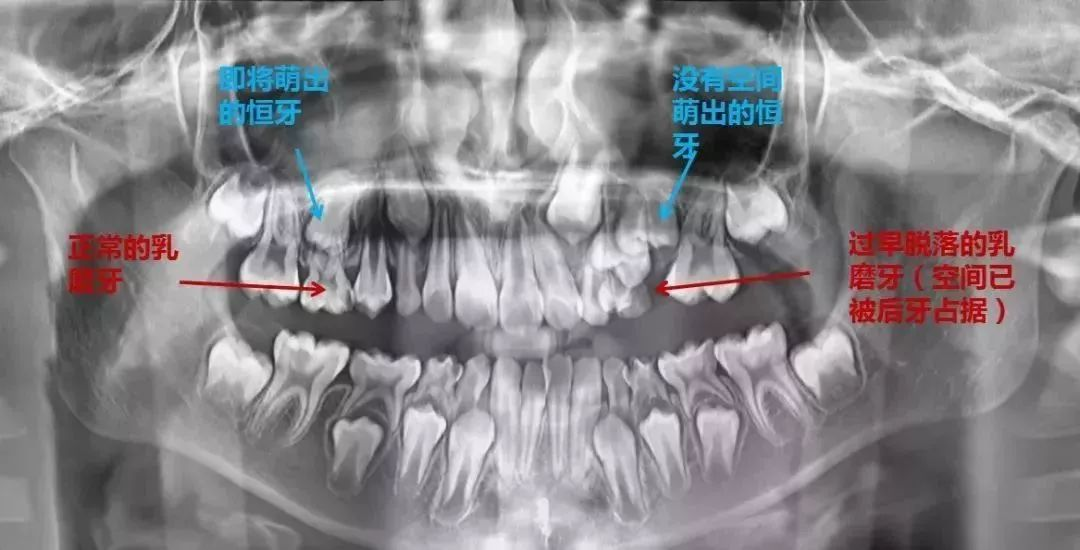

· 乳牙早失 (没到该掉的时间,牙掉了):恒牙失去导航,乱窜导致牙列拥挤!

2.缺失乳牙需戴间隙保持器 ,给未萌出的恒牙留位置,一个萝卜一个坑,坑位可得占住了!

乳牙早掉:牙槽骨缺乏刺激→恒牙萌出空间不足。